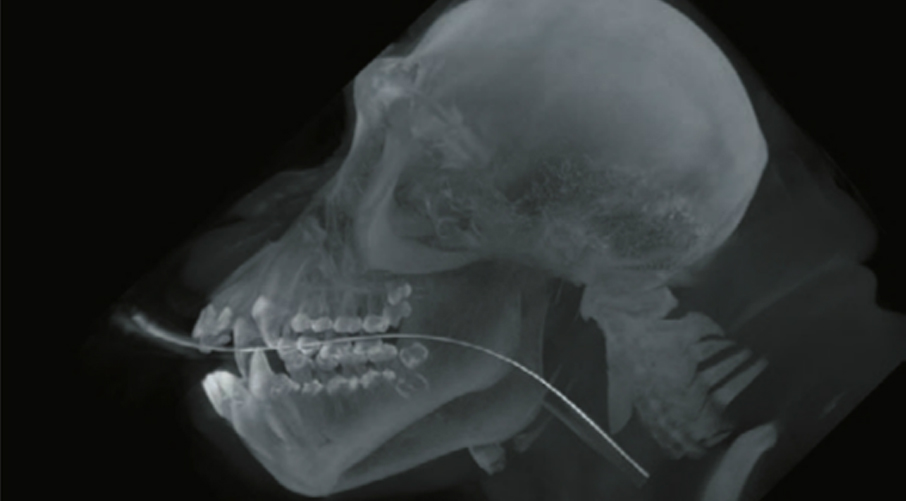

Mobile Pet Imaging Featured on Nat Geo Wild, for CT Scan of a Marmoset.